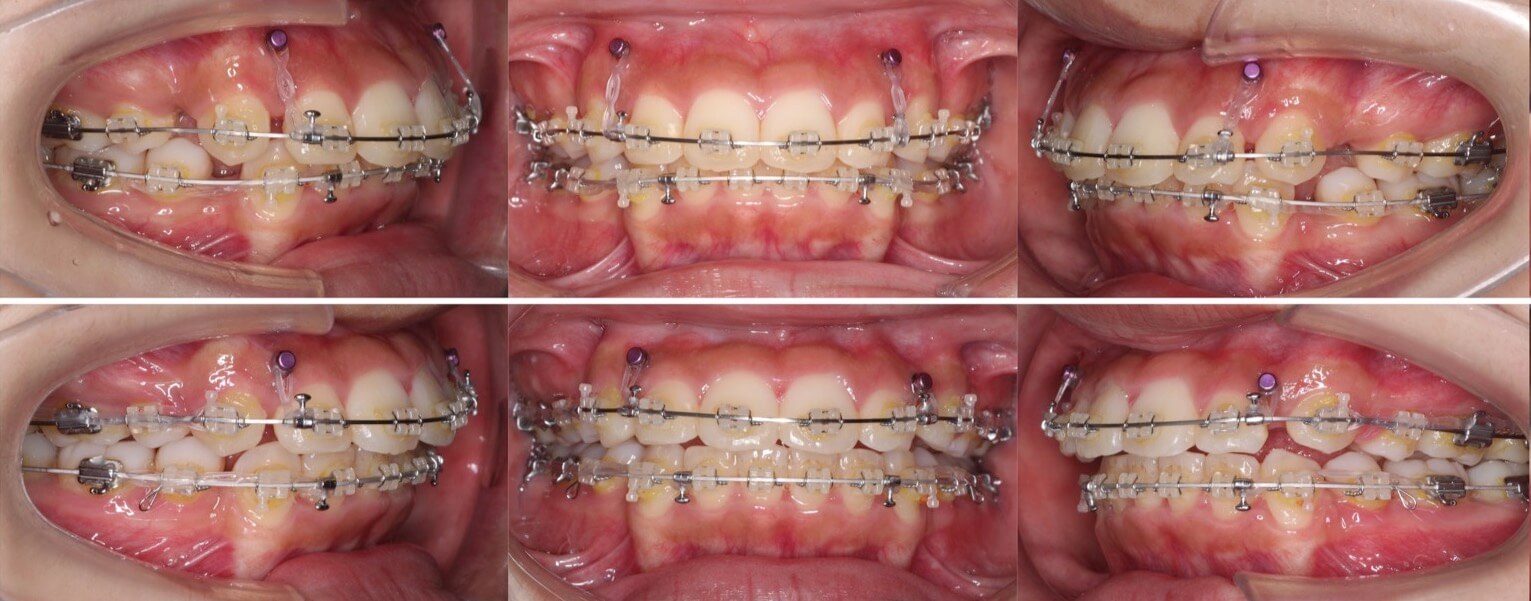

「男性は顔が引き締まる」

高校生男性・唇側矯正装置・下あご後退型

当初は、抜歯矯正治療にするかしないかで、治療方針に迷ったケースですが、最終的には患者さんの希望に沿って抜歯矯正治療にしました。歯の動きがゆっくりであったため、治療期間が3年を超えてしまいました。

治療方針:抜歯空隙の閉鎖(最大固定)

治療装置:唇側矯正装置

固定:歯科矯正用アンカースクリュー(頬側x2)

抜歯:上下第一小臼歯(計4本)

治療期間:3年4か月